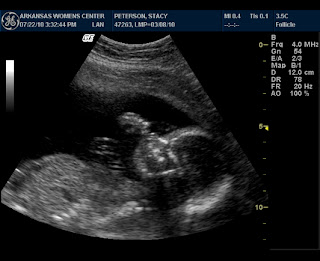

The other day, your mommy, daddy and grandpa all got to see you. It was so fun. Within minutes of the technician turning on the screen and looking at you, we got to see every little part of you. It was so exciting to see your little hands, your heart, your brain, your spine, your ribcage and everything in between! One of my most favorite parts though, was seeing your little feet! That was one of the most awesome things to see. I wish I had a still picture of them to print out just so I could look at them. I imagine seeing them in person and I get so excited! It was also such a relief to us to know that every part of you looked "beautiful" - and those are words from the doctor, not just your mommy and daddy. You weigh about 12 ounces, which is 3/4 of a pound, and your measurements are all spot on or slightly above where they should be. That is music to my ears, Baby! I am so glad you are healthy!

Arguably, your daddy would say that his favorite part of seeing you the other day is this:

He kept saying all along that he knew you were a little boy, and that he just needed "confirmation" from the doc. Your grandpa said that, too. I just had a feeling you were a little boy... a very strong feeling, so it wasn't a total surprise for any of us that you are. We've been calling you "he" all along. And now that we know, we can start planning more appropriately for you. We've begun cleaning out what will be your room, and your Aunt Mander and Grammy Roberts have already started on your wardrobe.